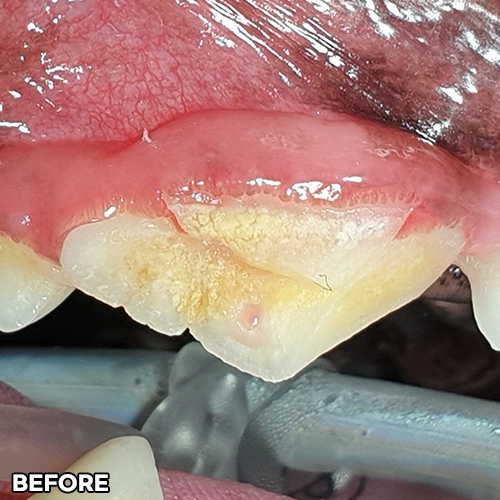

[심한 치아파절 자기치아파편으로 치아살리기]

샘플 샘플